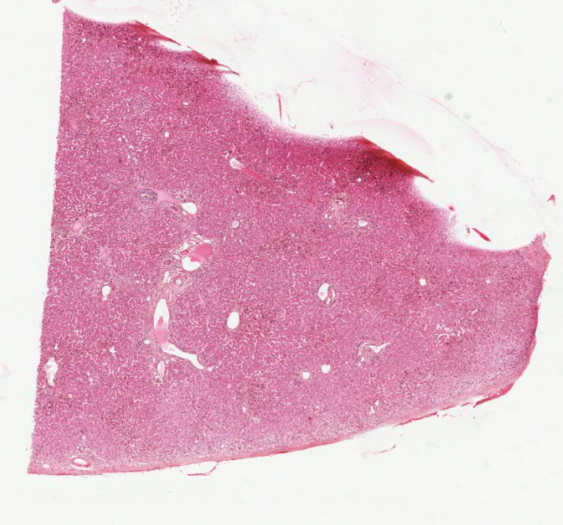

细胞和组织的适应与损伤

感染性藏毛囊肿